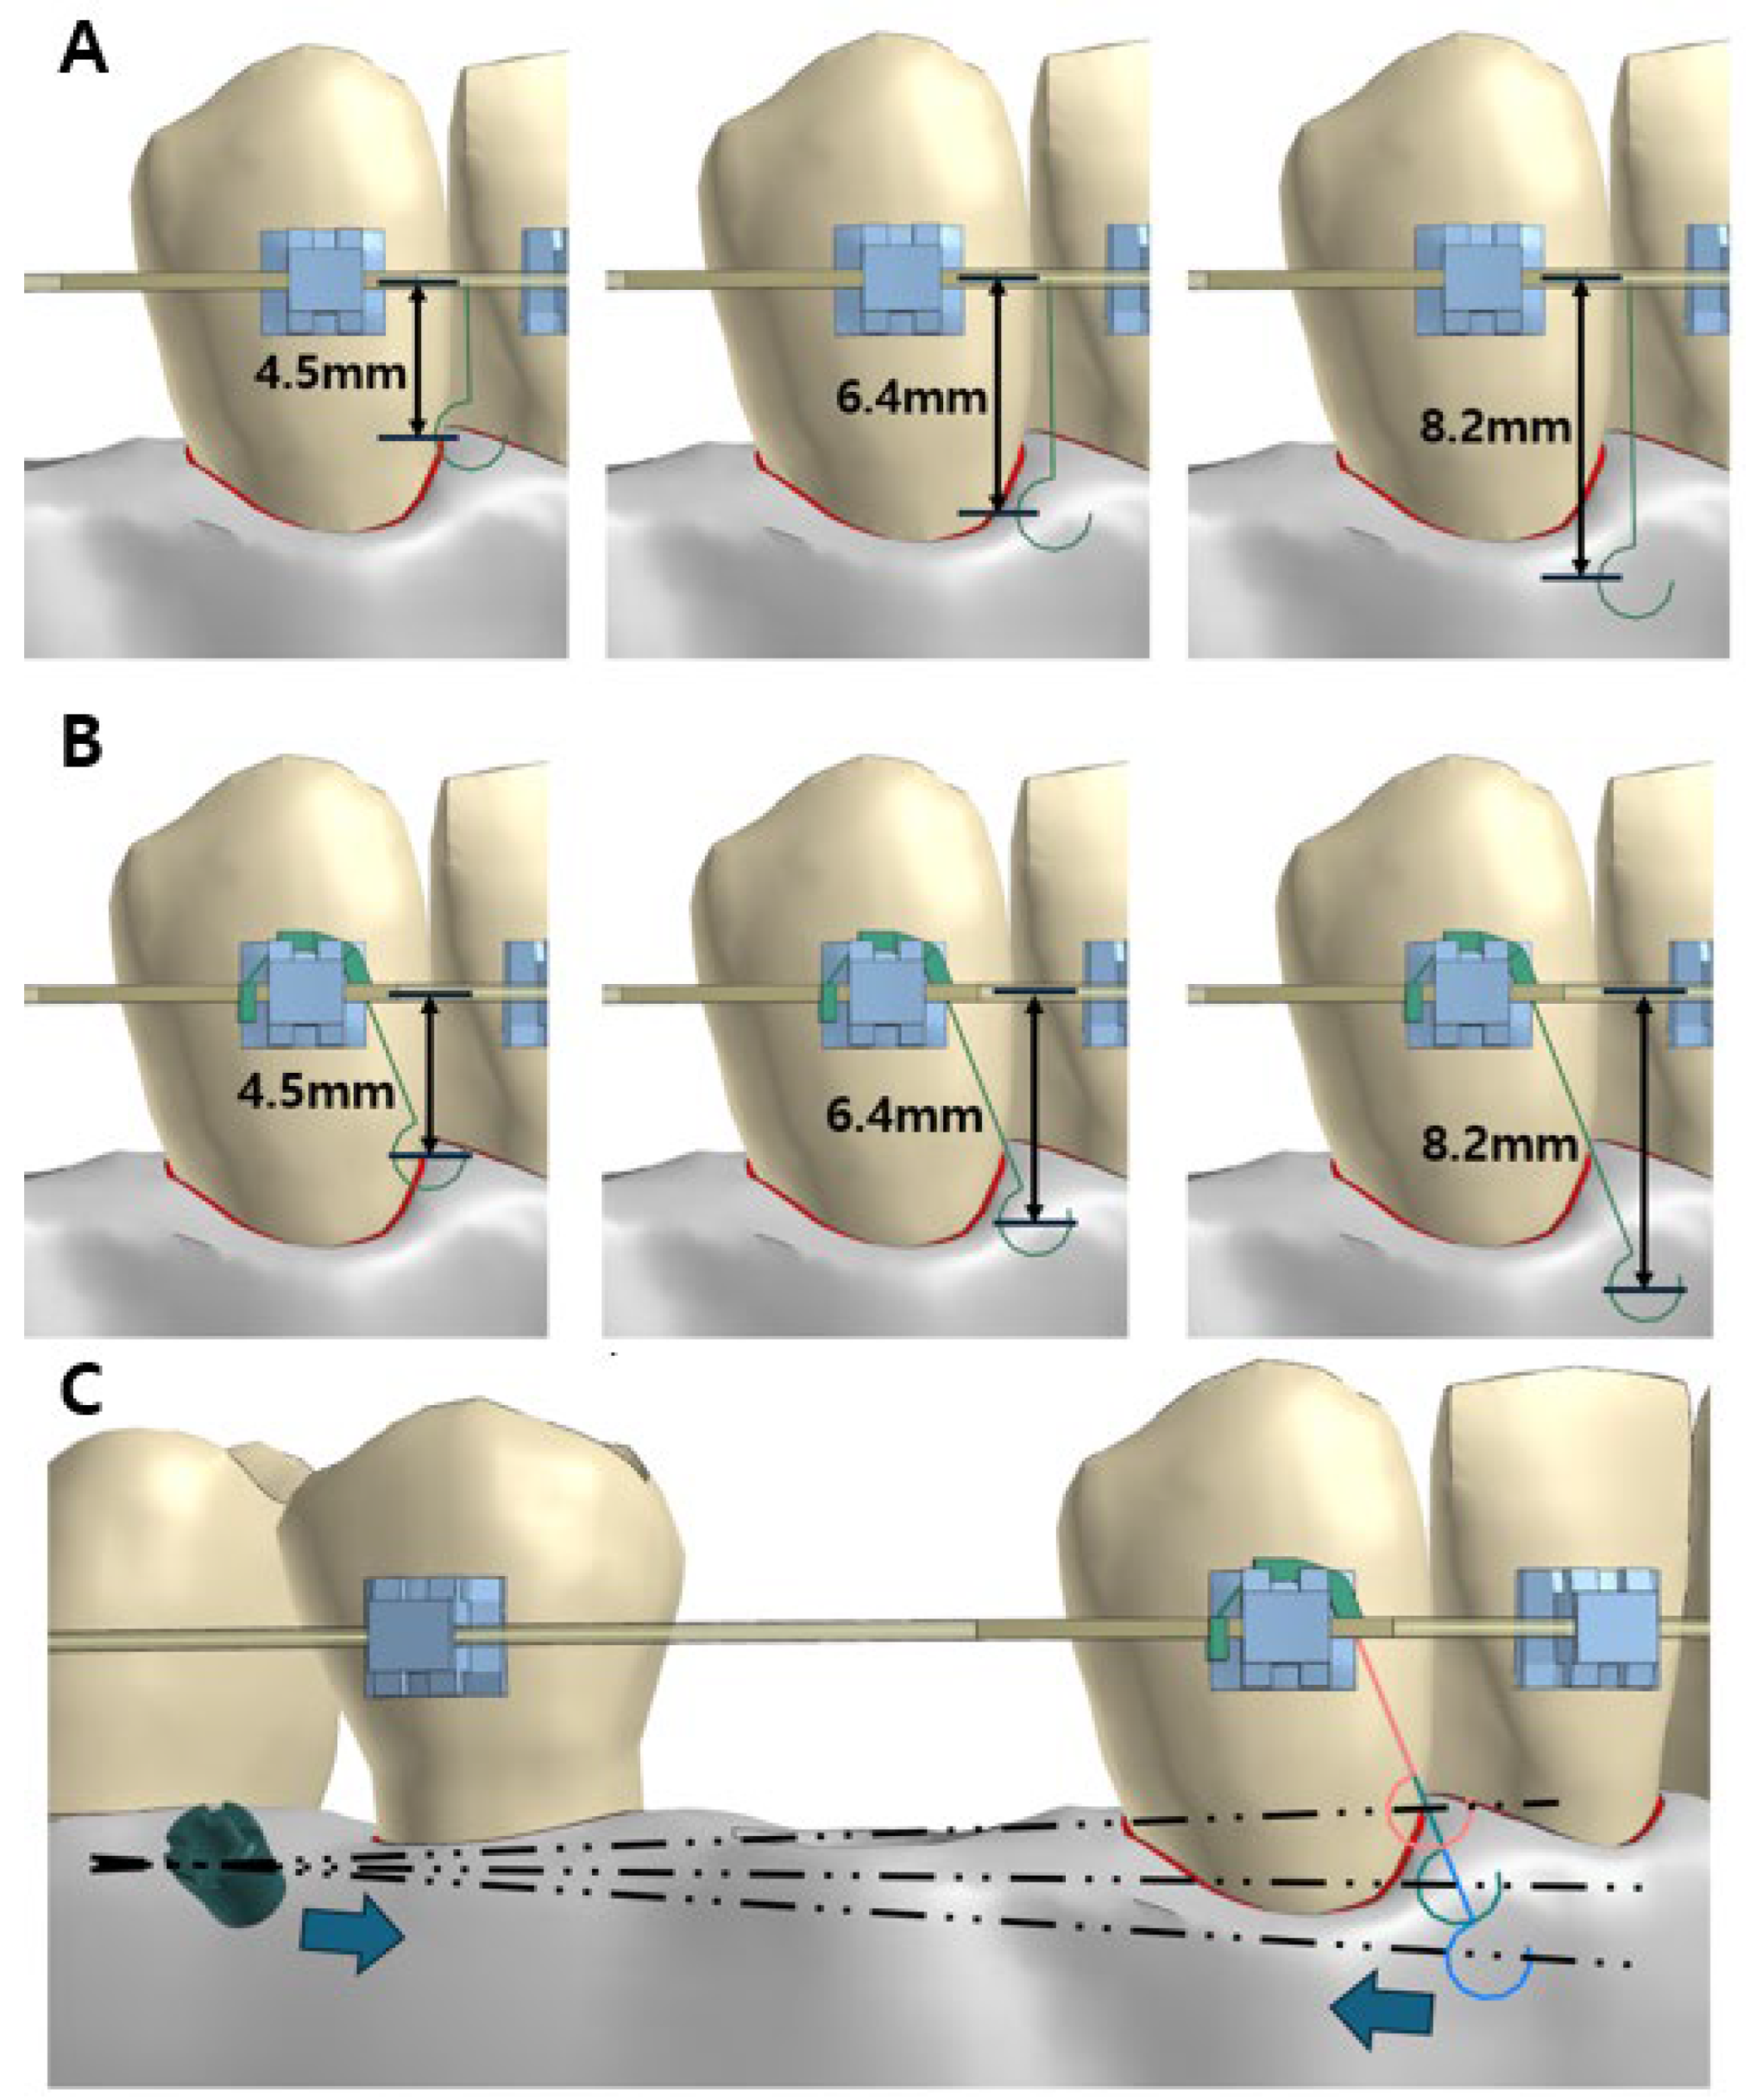

2.2. Experimental Design

- A model utilizing a power arm positioned between the lateral incisor and the canine on the main archwire;

- A model incorporating a lever jig.

2.5. Loading and Boundary Conditions